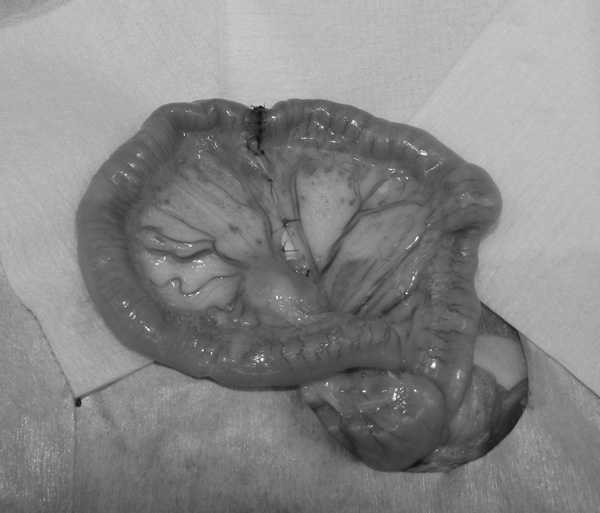

猫ちゃんが嘔吐と食欲不振の症状で来院されました。超音波画像から腫瘍による腸閉塞が疑われたため、開腹手術を行いました。病理組織検査の結果は「リンパ腫(高グレード、貫壁性)」でした。その後、抗がん剤による治療となりました。